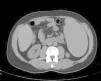

Abdominal tomography showed a 3700mL spleen at admission and 9 months after initiation of treatment, it reduced to 1358mL (64% reduction), demonstrating homogeneous parenchymal liver and spleen without portal hypertension (Figs. 1 and 2).